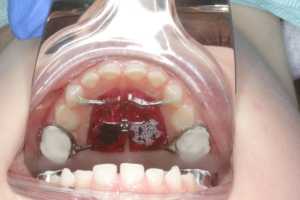

Аппарат устанавливается так, чтоб его основа была по центру нёба. Фиксация основы производится благодаря кольцам, которые надеваются на опорные зубы. Установленный аппарат создаёт определённое давление на челюстные дуги, постепенно расширяя верхнюю челюсть в поперечном направлении и тем самым делая её шире. Увеличивается нагрузка давления при помощи металлического винта, который находится в основе системы. Пациенту составляется график, когда именно и насколько нужно сделать обороты винта.

Когда половинки челюсти расходятся, на месте шва начинает образовываться свободное пространство. Постепенно оно заполняется новообразовавшейся костной тканью, которая костенеет и не позволяет в будущем двум половинкам принять прежнее положение. В процессе расширения нёба, между зубными единицами начнёт образовываться свободное пространство. Особенно это заметно между передними резцами. Этого не избежать. Решается проблема дальнейшей корректировкой брекетами (или иными ортодонтическими конструкциями).

- Быстрые результаты. Уже через 2 недели после фиксации системы можно наблюдать изменения в размере нёба.

- Короткие сроки лечения. В большинстве случаев для получения положительного результата хватает 2 месяца. Правда, для его устойчивости придётся ещё проносить конструкцию месяца 3, но винт уже не подкручивается, поэтому и давление на челюсть не оказывается.

Наблюдать первые результаты можно уже через 2-3 недели. Не забываем, чтоб образовавшаяся на месте шва щель заполнилась новой костной массой, нужно дополнительное время. Общие сроки ношения аппарата в среднем составляют полгода.

Активации чаще всего производятся 1-2 раза в день. Сроки активации в среднем 3-4 недели. За это время винт практически полностью раскручивается. Но помним, что это стандартый протокол лечения, могут быть индивидуальные корректировки в зависимости от конкретной ситуации в полости рта.

Далее винт «стабилизируется», т.е. заливается специальным материалом для того, чтобы после прекращения его раскручивания он стал неподвижным.